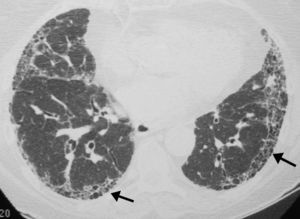

Es la prueba fundamental para el diagnóstico de la FPI al identificar los hallazgos típicos del patrón de NIU establecidos por el consenso oficial ATS/ERS/JRS/ALAT 20111 (tabla 3) (fig. 6).

Se recomienda la lectura radiológica utilizando una terminología descriptiva basada en la correlación radiológico-patológica, como la aconsejada por la sociedad Fleischner15. La tomografía axial computarizada de alta resolución (TACAR) tiene un valor predictivo positivo en el diagnóstico de la NIU del 90-100%. Además puede mostrar la presencia de comorbilidades como el enfisema, la hipertensión pulmonar o el cáncer de pulmón.